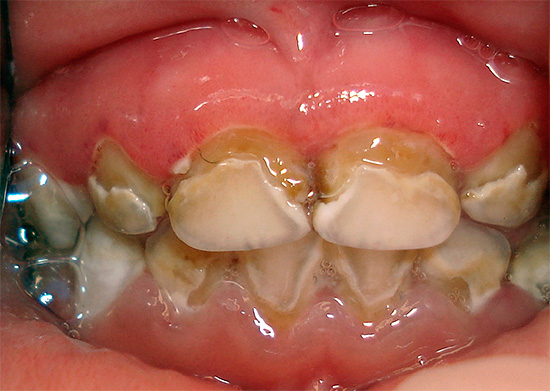

Oggi, a causa della popolarità della cura orale e della disponibilità di servizi dentali, la malattia è diventata meno comune, ma il problema è ancora rilevante nelle aree rurali e nei bambini in età scolare, quando quasi tutti i denti di un bambino sono affetti da carie (vedi l'esempio nella foto), e i genitori non sanno cosa fare in una situazione del genere.

Oltre al fatto che la carie è pericolosa per la salute, provoca dolore e limita la scelta del cibo, è anche un grave problema estetico. La foto sotto mostra un esempio di carie generalizzata:

La foto sotto mostra un altro esempio di corsa carie dei denti decidui in un bambino: